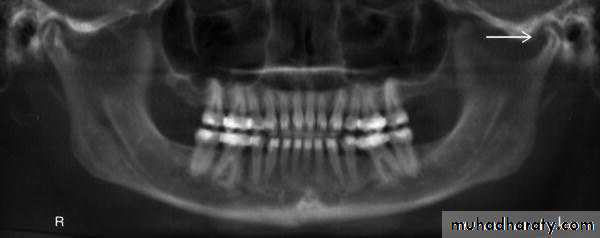

OPG: showing bilateral dislocation of the

condyles (open arrows) out of the glenoid fossae (white arrows).Developmental anomalies: